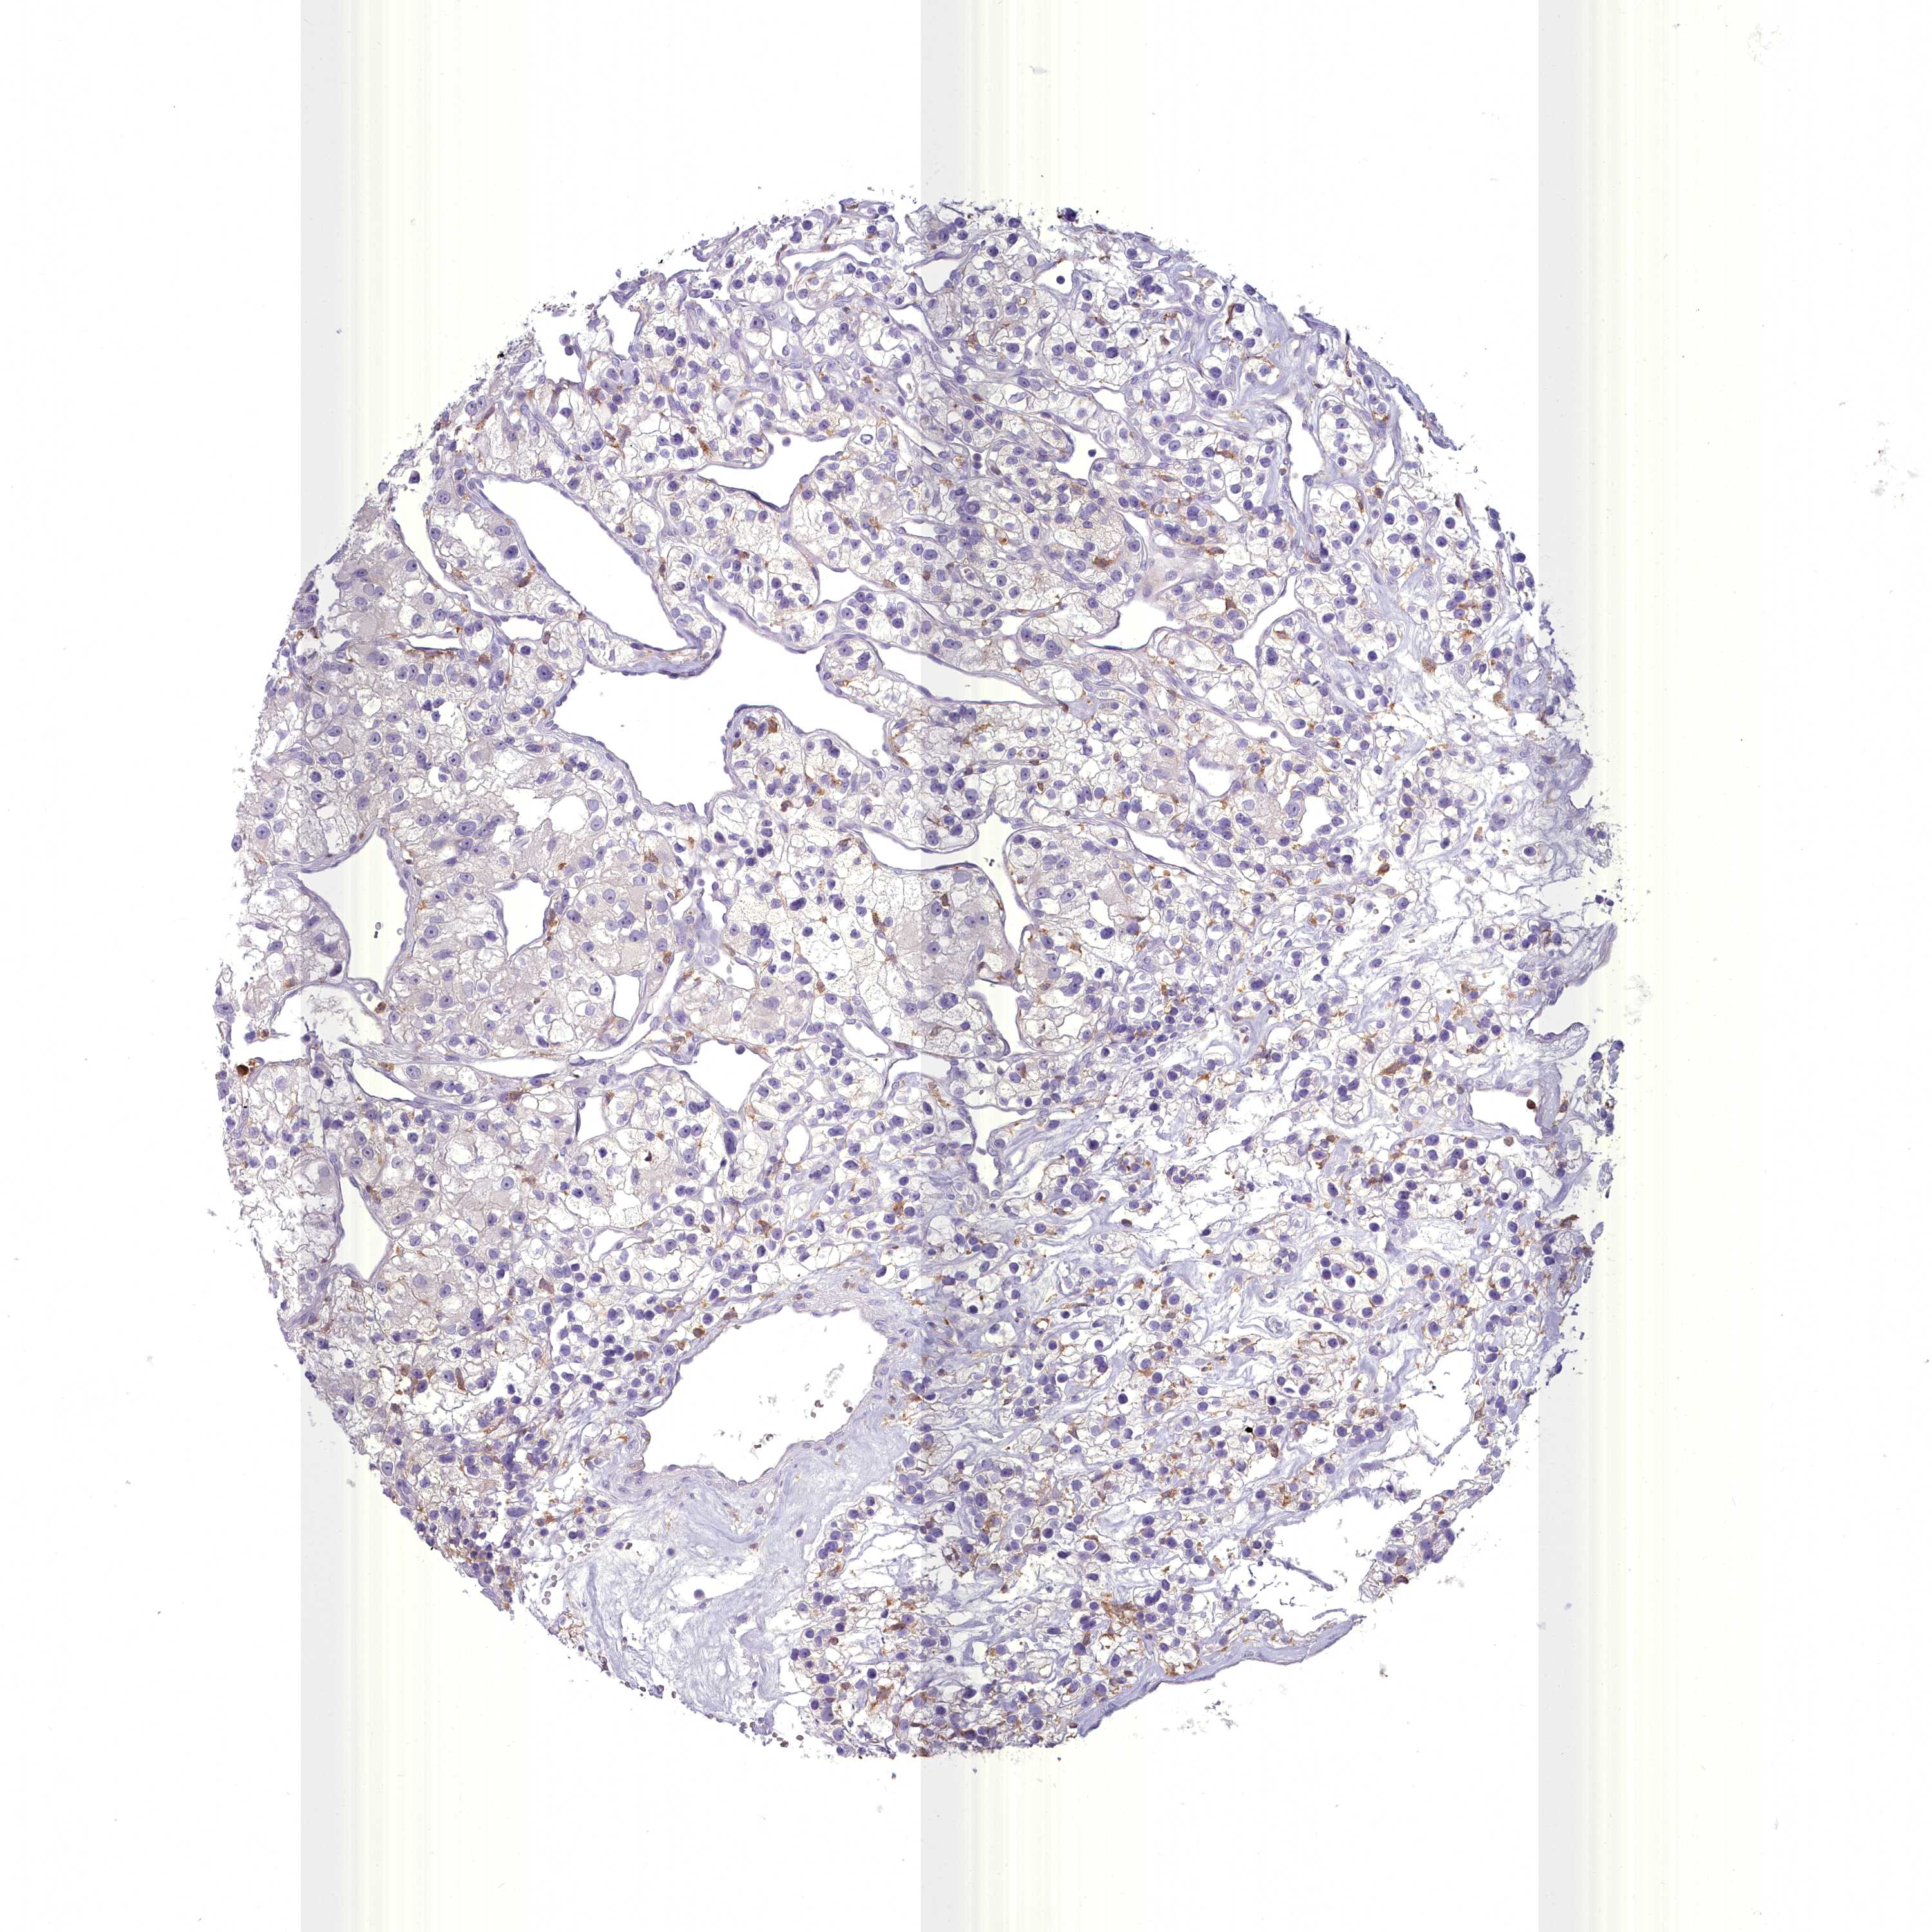

CANCER RENAL CANCER Show tissue menu

KICH TCGA KIRC TCGA KIRC VALIDATION KIRP TCGA PROTEIN RCC CPTAC PROTEIN EXPRESSION

BLNK is potential prognostic, high expression is favorable in Kidney Renal Clear Cell Carcinoma (TCGA)